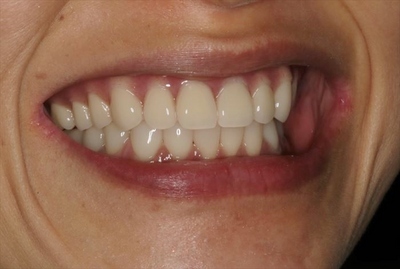

IMG_6899_R26.JPG

初診時の状態です。(2019.05.10)

初診時(2019.05.10)